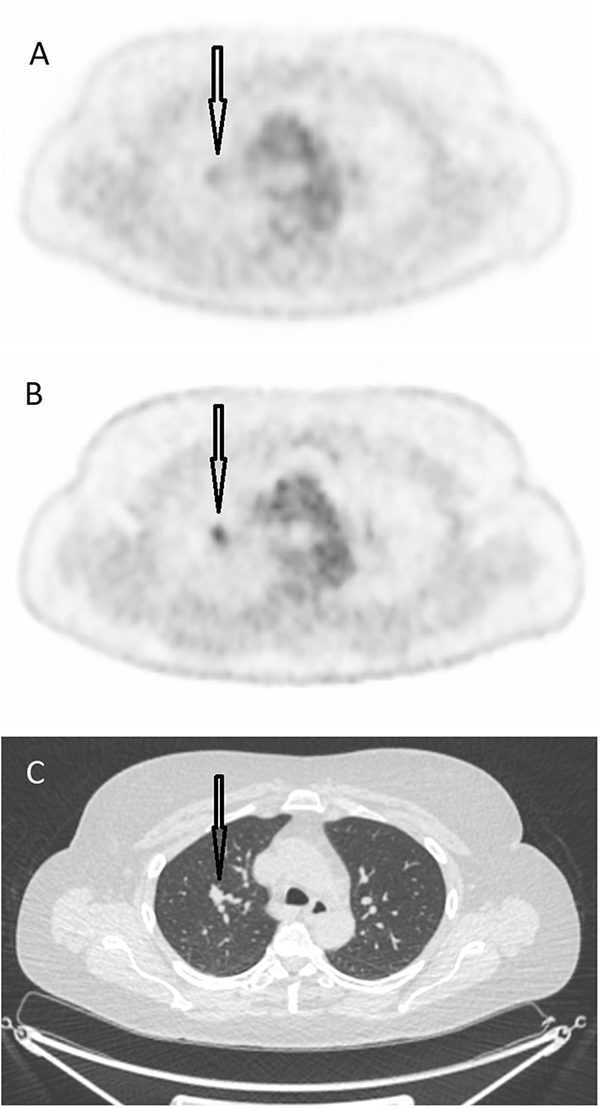

図1. A) 従来のPET/CTスキャナによる画像、B) Discovery MIによる同じ画像、C) CT画像。

矢印は右肺のがんを示し、B)ではがんへのFDG集積が強く描出されている。

FDG PET/CTは、ポジトロン放射断層撮影(PET)とX線コンピュータ断層撮影(CT)を組み合わせた画像診断装置です。FDG(フルオロデオキシグルコース、[18F]fluorodeoxyglucose)は、がん細胞が健康な細胞よりも多くの糖を消費する性質を利用したトレーサー(追跡物質)です。まず、検査前に経静脈的にFDGを注射します。そして、がんに多く集まったFDGの一つひとつに由来する陽電子から、180度方向に放出される2本の線をPETスキャナで検出し、がんを可視化します。同時に、CTスキャナによりX線を用いて体の断層画像を撮影することで、FDGの集まっている部位を体の構造情報と合わせて詳細に評価することができます。当院のPET/CT装置は、PETスキャナ に半導体検出器が搭載されており(米国GEヘルスケア社製Discovery MI)、従来のPETスキャナと比較して感度が著しく向上しています(例を図1と図2に示します)。